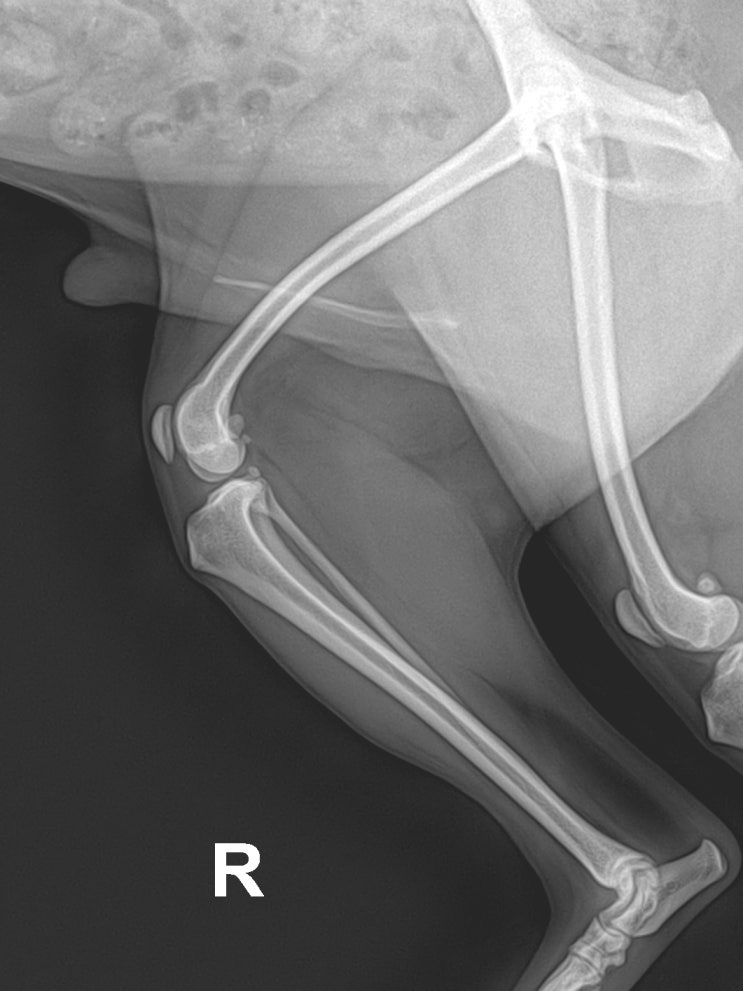

강아지 슬개골 탈구 4 기 수술 8개월 전후 비교 / 반려견 고관절 아탈구 수술 / 애완견 골반 수술 & 슬개골 수술 후유증? / 어린 강아지 무릎 수술 & 관절 주사 치료

안녕하세요~ 굿파파 수의사입니다. 오늘은 여름이 느껴지는 오후네요~ 시원한 커피 한 잔과 함께 ~ 행복한 ...